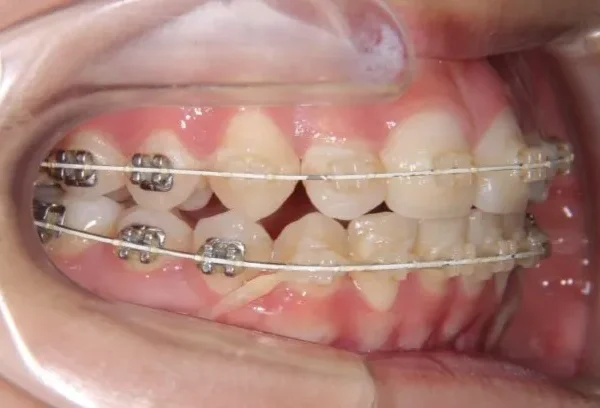

• 治療経過1

治療経過1

診断名 叢生・開咬・上下顎前突 装置名

マルチブラケット装置

歯科矯正用アンカースクリュー